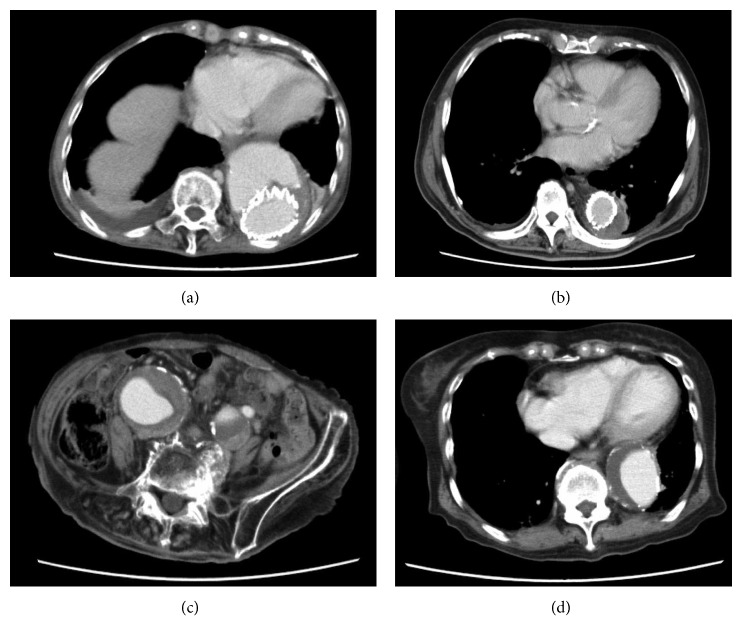

Patient 1 was an 84-year-old woman who had undergone thoracic endovascular aortic repair (TEVAR) for an aortic dissected aneurysm (Figure 1(a)) and was hospitalized for thrombocytopenia and abnormal coagulation. Her laboratory data showed hemoglobin (Hb) 7.9 (reference; 11–16) g/dl, platelet count 79,000 (reference; 150,000–360,000)/μl, fibrinogen degradation product (FDP) of 101.5 (reference; <5) μg/ml, D-dimer of 49.8 (reference; <1.0) μg/ml, fibrinogen 98 (reference; 200–400) mg/dl, thrombin-antithrombin complex (TAT) 40.5 (reference; <3) ng/ml, and plasmin-α2 plasmin inhibitor complex (PIC) 12.7 (reference; <0.8) μg/ml. Prior to admission, she had been treated with warfarin. Our vascular surgeons regarded her aneurysm condition after TEVAR as inoperable. She was started on a continuous intravenous infusion of 10,000 units/day heparin and 250 mg twice daily intravenous tranexamic acid. This combination treatment was effective as her plasma FDP and D-dimer concentrations decreased while her fibrinogen level and platelet count increased (Figure 2). To facilitate her discharge, she was switched from intravenous to oral tranexamic acid (750 mg/day) and from intravenous to subcutaneous administration of heparin calcium (5,000 units twice daily), and warfarin was stopped. Although this combination was effective, the patient was intolerant of subcutaneous heparin calcium because of pain, and she was transitioned to oral rivaroxaban 15 mg/day for discharge from hospital.

Figure 1.

Contrast-enhanced axial CT findings showing aortic aneurysm/dissection in (a) Patient 1, showing a stent graft in the descending aorta; (b) Patient 2, showing a stent graft in the descending aorta; (c) Patient 3, showing aneurysms in the bilateral common and internal iliac arteries; and (d) Patient 4, showing an aneurysm in the descending aorta.

Patient 2 was an 87-year-old man who had undergone TEVAR for a Stanford type B aortic dissection 7 months earlier (Figure 1(b)). Thereafter, he was sent to a rehabilitation center, where his plasma FDP and D-dimer increased gradually, while fibrinogen and platelet count decreased, and anemia progressed. He received transfusions of packed red blood cell (PRBC) and platelet concentrate (PC) several times (precise units unknown), although the cause of his abnormal coagulopathy was not adequately assessed. Following persistent gingival bleeding for 2 weeks, he was transferred to our hospital for evaluation. His laboratory data showed Hb 7.9 g/dl, platelet count 73,000/μl, FDP 96.8 μg/ml, D-dimer 24 μg/ml, fibrinogen 73 mg/dl, TAT 58 ng/ml, and PIC 17.6 μg/ml. Following PRBC (4 units) infusion, he was treated with subcutaneous heparin calcium (5,000 units twice daily) and oral tranexamic acid (1,500 mg/day). After 1 week, his laboratory data improved, with Hb 9.1 g/dl, platelet count 146,000/μl, FDP 10.9 μg/ml, D-dimer 6.3 μg/ml, and fibrinogen 186 mg/dl. Later, he was successfully switched to oral rivaroxaban (15 mg/day) as maintenance treatment at the outpatient clinic (Figure 3).

Patient 3 was a 91-year-old woman, who was hospitalized for gingival bleeding. Her laboratory data showed Hb 8.4 g/dl, platelet count 100,000/μl, FDP 109 μg/ml, D-dimer 51.4 μg/ml, and fibrinogen 72 mg/dl. Enhanced CT revealed bilateral iliac aneurysms, with the right and left aneurysms having maximum diameters of 60.5 mm and 43.7 mm, respectively (Figure 1(c)). She was initially treated with PRBC (6 units) and fresh frozen plasma (FFP; 10 units), followed by intravenous tranexamic acid (250 mg four times daily) for 3 days. However, because these aneurysms were thought to be responsible for her coagulopathy and the patient was regarded eligible for surgery, EVAR operation was performed, after which her DIC resolved.

Patient 4 was an 83-year-old woman, who was hospitalized with gastrointestinal (GI) bleeding and dyspnea due to persistent chronic obstructive pulmonary disease. Her laboratory data showed Hb 3.0 g/dl, platelet count 62,000/μl, mean corpuscular volume 82.9 (reference; 83–100) fl, serum blood urea nitrogen 98.0 (reference; 7.8–18.9) mg/dl, and creatinine 1.41 (reference; 0.45–0.82) mg/dl. Upper GI endoscopy showed bleeding in the duodenum which continued after admission, and it was found to be DIC-related. Her plasma FDP was 177 µg/ml, D-dimer 81.7 µg/ml, TAT 69.2 ng/ml, and PIC 12.6 µg/ml. Eventually, she was identified with an aortic aneurysm (Figure 1(d)), and hemostasis laboratory abnormalities were attributed to be related to her aortic aneurysm. Surgical treatment of her aortic aneurysm was discussed; however, her general condition was poor, and because of repeat GI bleedings, she required upper GI endoscopy 13 times over 23 days for emergency hemostasis and with incomplete and persistent DIC. During the period, she received PRBC (36 units), FFP (70 units), and PC (50 units) transfusions. On day 38, she was started on systemic treatment for DIC, consisting of intravenous heparin (12,000 U/day) and intravenous tranexamic acid (250 mg twice daily), which resulted in rapid improvement of laboratory data. Unfortunately, the patient died of aspiration pneumonia 2 days later.